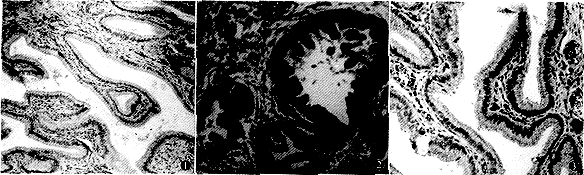

【摘要】 目的 检测P-糖蛋白在不同胆囊组织中的表达,以探讨该蛋白与胆囊癌抗化疗特性的关系及作为胆囊癌生物标志物的潜在价值。方法 采用碱性磷酸酶-抗碱性磷酸酶(APAAP)的免疫组化方法,用二种决定簇不同的抗人P-糖蛋白的单克隆抗体JSB-1和UIC-2,检测26例胆囊癌、14例胆囊良性肿瘤及9例正常胆囊组织中P-糖蛋白的表达情况,并分析其表达程度与不同临床资料的相关关系。结果 单抗JSB-1测得P-糖蛋白在胆囊癌中表达的阳性率为76.9%,显著高于胆囊良性肿瘤组及正常胆囊组(阳性率分别为35.7%和33.3%,P<0.05)。单抗UIC-2测得P-糖蛋白在胆囊癌中表达的阳性率为69.2%,也显著高于胆囊良性肿瘤组及正常胆囊组(阳性率分别为21.4%和11.1%,P<0.01)。P-糖蛋白的表达阳性率与胆囊癌的TNM分期及胆囊良恶性肿瘤的病理类型均无相关关系。结论 P-糖蛋白在胆囊恶性肿瘤中的过表达,提示其在胆囊癌对化疗不敏感的特性中起着重要作用,同时P-糖蛋白在不同胆囊组织中表达的显著差异性 ......